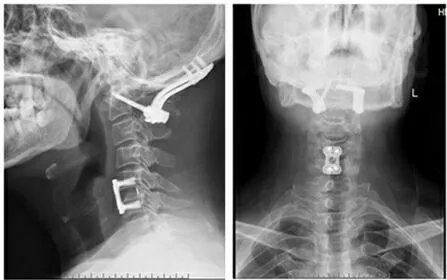

郑州市骨科医院脊柱二科科室简介